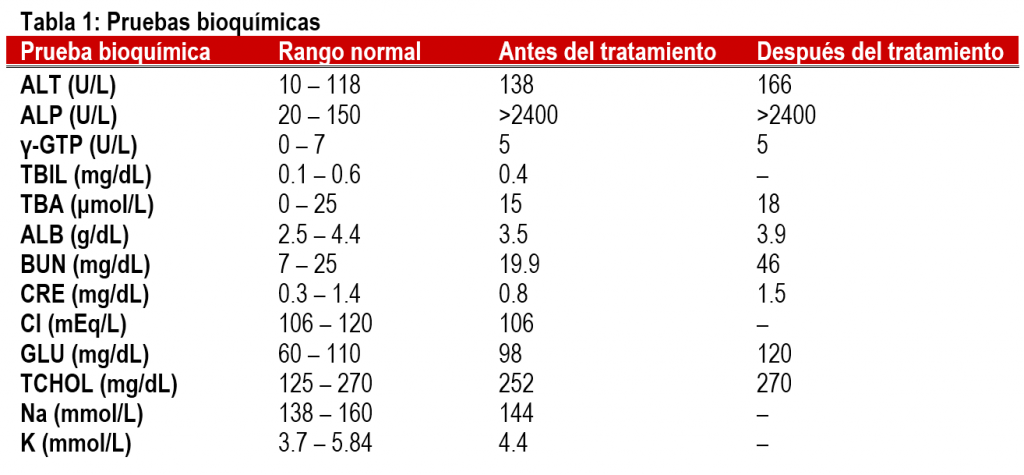

Shih, un Shih-Tzu macho, castrado, de 16 años sufría de insuficiencia cardíaca grave y metabolismo lipídico anormal. Shih había estado recibiendo tratamiento desde los 12 años y a la edad de 14 años se confirmó que tenía un aumento de la ALT y la ALP (Tabla 1).

Se sospechó que padecía de circulación de un volumen inadecuado de sangre debido a la insuficiencia cardíaca, metabolismo lipídico anormal y deterioro de la función hepatobiliar secundario a un trastorno de la vesícula biliar (cistomixoma). Sin embargo, el nivel de albúmina era normal al igual que el nivel de ácido biliar total (TBA); por lo tanto, era poco probable la presencia de una enfermedad hepática primaria.

En consecuencia, se pensó que se trataba del síndrome de Cushing debido al nivel anormalmente alto de ALP y a otros elementos de la lista del diagnóstico diferencial. Una prueba de estimulación con ACTH confirmó el trastorno. El nivel volvió a su rango normal después de un tratamiento con trilostano durante un mes (Tabla 2).

Se continuó el tratamiento del síndrome de Cushing utilizando trilostano. Cuando Shih cumplió 16 años, se produjo un aumento de polidipsia/poliuria. Un análisis de sangre indicó un aumento de la ALT y el BUN (la ALP también estuvo elevada) (Tabla 1).

Se tuvo que determinar si los cambios químicos y de PU/PD se debían al síndrome de Cushing, a la necesidad de cambiar la medicación o si había un trastorno hepatobiliar. Debido a que el nivel de TBA era normal, en lugar de un trastorno hepatobiliar, se determinó tentativamente que se trataba de un efecto producido por un tratamiento inadecuado para el síndrome de Cushing. Se recomendó realizar una prueba de estimulación con ACTH (Tabla 3) y una ecografía abdominal. El propietario no dudó en aceptar ya que las pruebas de TBA indicaban la necesidad de hacer esto.

Sobre la base de los resultados obtenidos a partir de la estimulación con ACTH y la ecografía abdominal, se diagnosticó hipercortisolemia debido al tumor en el lado craneal de la glándula suprarrenal izquierda. Aunque se le recomendó al propietario proceder a la extracción del tumor, no se recibió su consentimiento debido a la edad del perro. Por lo tanto, se aumentó la dosis del trilostano como un método de tratamiento médico. Como resultado de este tratamiento, el nivel de ALT disminuyó y se estabilizó posteriormente.